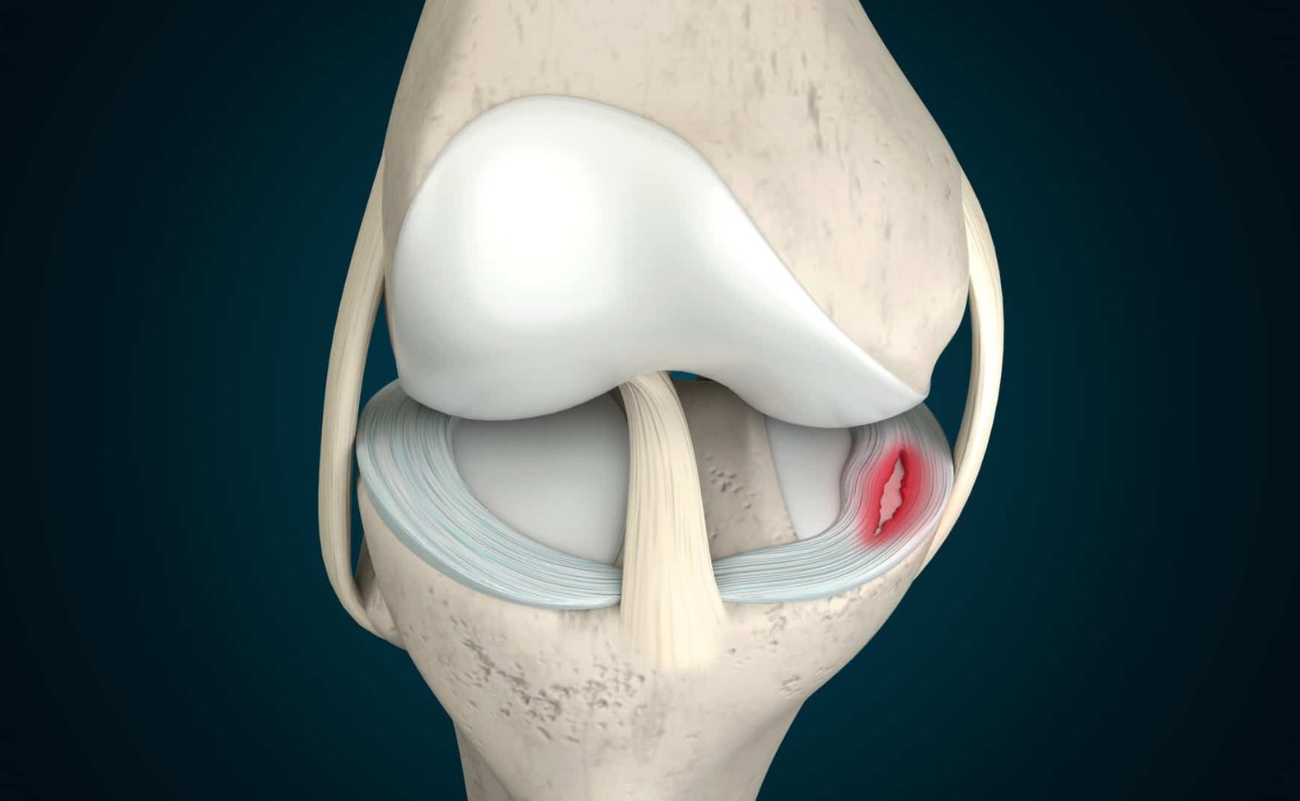

Ligament injuries

Ligaments are tough tissues that connect bones. The four main ligament in your knee are Anterior cruciate ligament (ACL), Posterior curciate ligament (PCL), Lateral collateral ligament (LCL) and Medial collateral ligament (MCL). Of these the ACL is injured the most.

Understanding Meniscus Tears: Causes, Symptoms, and Treatment Options

The meniscus is a C-shaped piece of cartilage in the knee joint that acts as a cushion between the femur (thighbone) and tibia (shinbone). It plays a crucial role in absorbing shock, providing stability,